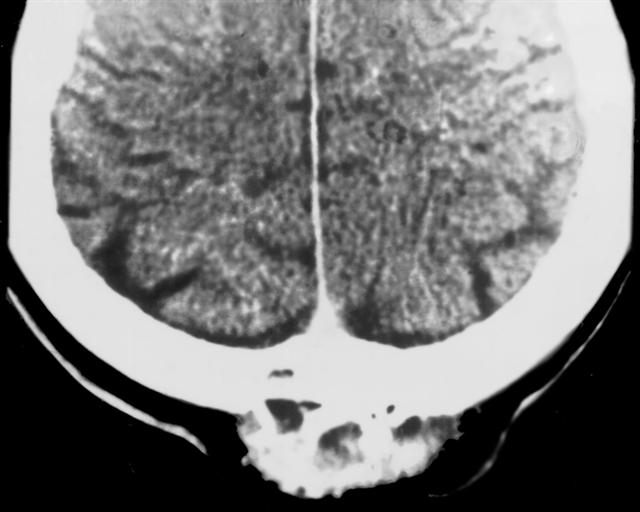

Рис. 10. Аксиальная компьютерная томограмма больного с остеогенной саркомой в теменно-затылочной области: опухоль врастает в мягкие ткани головы с образованием остеоидной и костной ткани в массе опухоли.